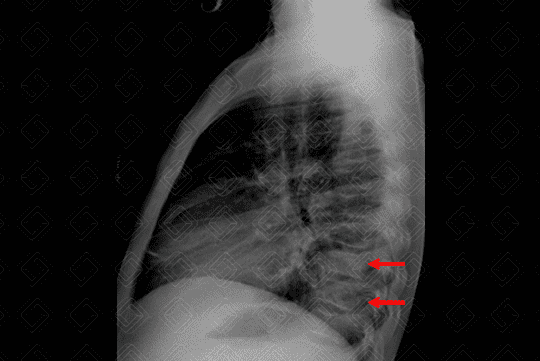

Descrição da lesão: Radiografia de tórax: incidências AP e perfil (figuras 1 e 2, respectivamente). Observa-se na radiografia em AP (figura 1): opacidade arredondada retrocardíaca (setas brancas). Ao analisar a radiografia em perfil (figura 2), deve-se estar atento ao gradiente normal da coluna (os corpos vertebrais superiores devem ser "mais brancos", ou seja, mais radiopacos quando comparados aos inferiores, que naturalmente são mais hipertransparentes). Neste caso, observamos que os corpos vertebrais inferiores estão mais brancos que o habitual, ou seja, o foco de consolidação encontra-se no lobo inferior do pulmão (setas vermelhas). Observação : Sabemos que a consolidação está no pulmão esquerdo, pois observa-se "apagamento" do diafragma esquerdo no perfil, indicando que a pneumonia retrocardíaca visualizada no AP de tórax encontra-se no lobo inferior do pulmão esquerdo.